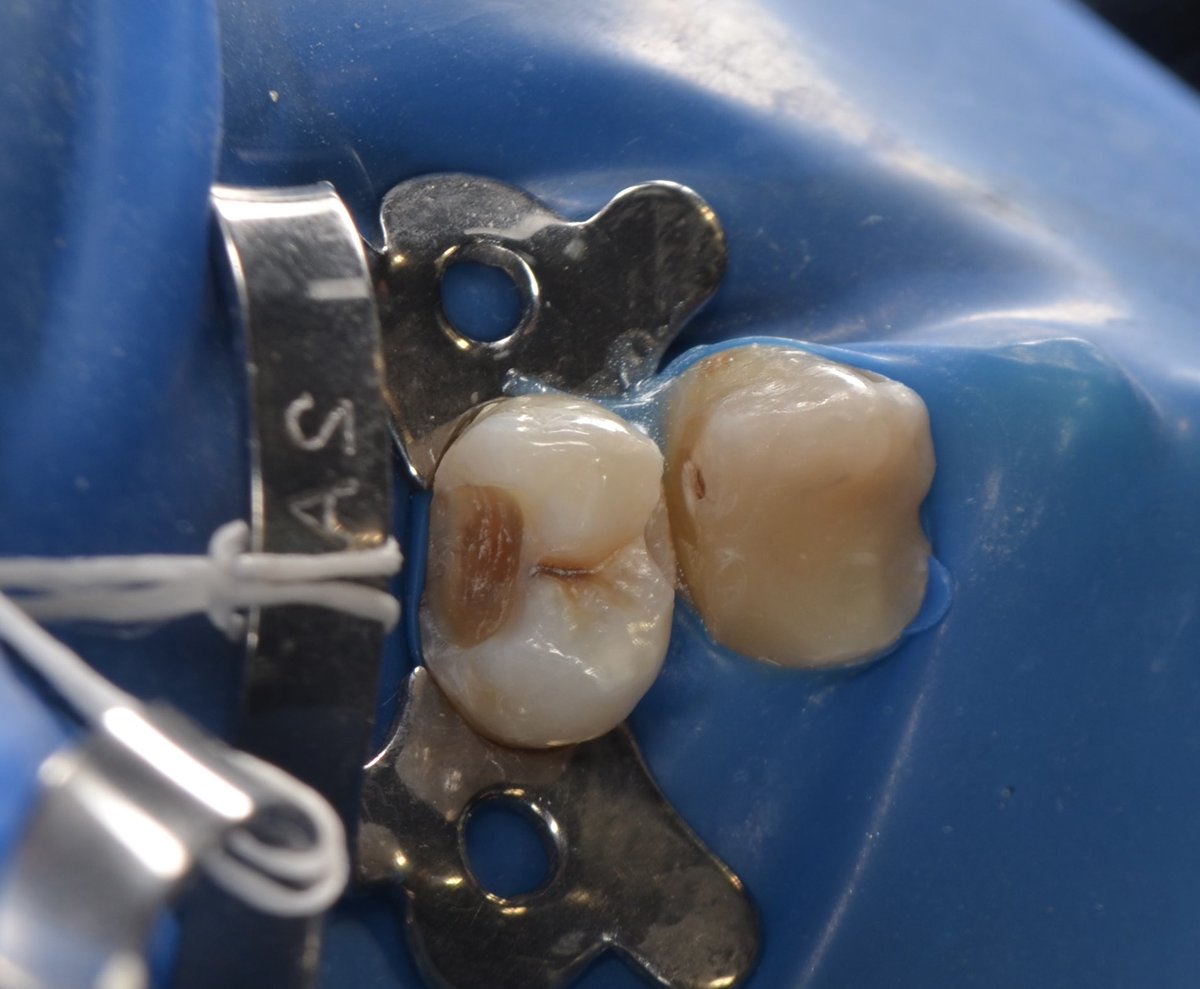

Successfully completed endodontic treatment on #36 with Radix Entomolaris, a challenging and rewarding case ✨

Grateful to have performed it under the supervision of @DrKhawlahSays and @HananShu

Thank you for your guidance and continuous support in advancing our clinical skills.